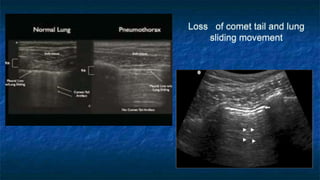

Lung Scanning for Pneumothorax

Comet tails sign

and sliding lung

Loss of comet tail and lung

sliding movement

Lung Scanning forPneumothorax Comet tails sign and sliding lung

Loss of comettail and lung sliding movement